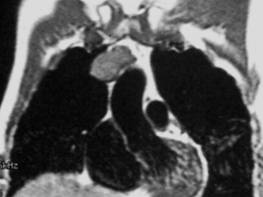

3 .颈胸部病变:由于血管的流空效应及纵隔内脂肪的高信号特点可清晰显示纵隔、肺门、咽、喉、甲状腺、颈部淋巴结、血管及颈部肌肉,对纵隔及肺门淋巴结肿大、占位性病变、颈部病变诊断具有重要诊断价值。但对于肺内钙化及肺实质及肺间质小病灶的检出远不如 CT 。

图: 纵隔 肿瘤